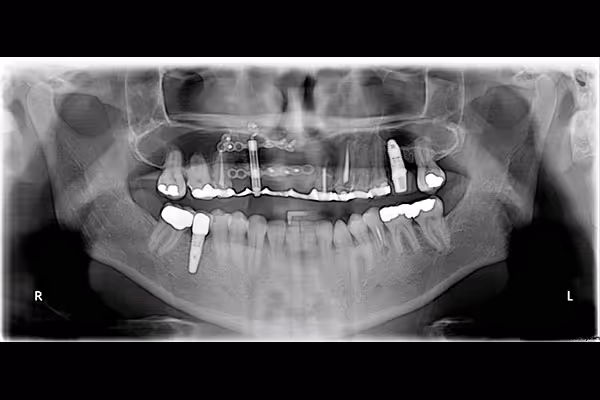

Distraction osteogenesis is a life-changing procedure for facial and dental defects. It restores oral deformities by lengthening an inadequate jawbone. The technique entails cutting the affected jawbone and placing a distractor between the bone fragments. New bone will start growing naturally to fill the gap between the bone segments, leading to a longer, healthier, and denser jawline. The regenerated bone provides a sturdy foundation for placing dental implants and other dental restorations.

Distraction osteogenesis involves separating a shortened jawbone into two bone segments. Our maxillofacial surgeon will incise the target jawbone via a process called osteotomy. We will then place devices called distractors between the bone fragments under the gum to separate the segments and create a gap. Sometimes, we attach them to the jawline outside the skin and fasten them to keep them in place. Once placed, your body will regenerate new bone to fill the gap. We may have to turn and tighten the distractors several times during healing to stimulate bone growth. Our oral surgeon will place the necessary dental restorations after you grow an adequate jawbone.

Distraction osteogenesis has several phases and requires multiple visits to our clinic. After a comprehensive dental examination, our surgeon will administer general anesthesia. We will then incise the target jawbone and insert distractors to create two bone segments. We call this stage the osteotomy phase. We will then pre-schedule your next visit as you go through a seven day healing period.The next phase is the activation stage. During this procedure, we will turn the distractors to ensure they deliver the projected results. We may adjust the distractors by 0.5 millimeters if we want your jawbone to grow at the same rate daily. The last step is the consolidation phase, which entails stabilizing the distractors and using them as fixation devices. The entire distraction process might take one to three months.